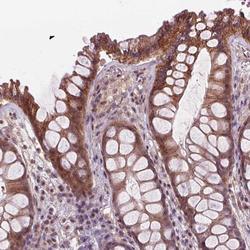

- Immunohistochemical staining of UBAP1L in human rectal tissue shows strong cytoplasmic positivity in glandular cells. Samples were probed using an UBAP1L Polyclonal Antibody (Product # PA5-64217).